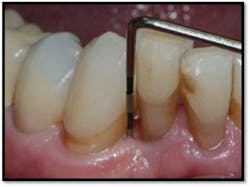

Severe bone loss #26, 8mm DF, 5mm straight facial, +2 mobility

LL Quadrant#27M, now 2mm reduced from 6mm, tissue tight and firm

#26 DF, now 2mm from 8mm

#26 F now 2mm. All tissue is light pink, tight and firm.

Bone fill #26 and 27,no mobility